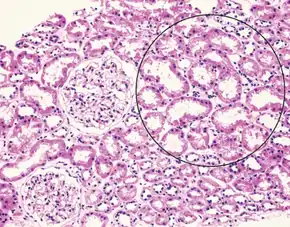

| Liver histology is altered in HRS while kidney histology is normal. The upper image is a trichrome stain (chicken wire appearance) of cirrhosis of the liver, the most common cause of HRS. | |

Hepatorenal syndrome usually affects individuals with cirrhosis and elevated pressures in the portal vein system (termed portal hypertension). While HRS may develop in any type of cirrhosis, it is most common in individuals with alcoholic cirrhosis, particularly if there is concomitant alcoholic hepatitis identifiable on liver biopsies.[5] HRS can also occur in individuals without cirrhosis, but with acute onset of liver failure, termed fulminant liver failure.[7][5]

Many other diseases of the kidney are associated with liver disease and must be excluded before making a diagnosis of hepatorenal syndrome. Individuals with pre-renal kidney failure do not have damage to the kidneys, but as in individuals with HRS, have kidney dysfunction due to decreased blood flow to the kidneys. Also, similarly to HRS, pre-renal kidney failure causes the formation of urine that has a very low sodium concentration. In contrast to HRS, however, pre-renal kidney failure usually responds to treatment with intravenous fluids, resulting in reduction in serum creatinine and increased excretion of sodium.[7] Acute tubular necrosis (ATN) involves damage to the tubules of the kidney, and can be a complication in individuals with cirrhosis, because of exposure to toxic medications or the development of decreased blood pressure. Because of the damage to the tubules, ATN affected kidneys usually are unable to maximally resorb sodium from the urine. As a result, ATN can be distinguished from HRS on the basis of laboratory testing, as individuals with ATN will have urine sodium measurements that are much higher than in HRS; however, this may not always be the case in cirrhotics.[18] Individuals with ATN also may have evidence of hyaline casts or muddy-brown casts in the urine on microscopy, whereas the urine of individuals with HRS is typically devoid of cellular material, as the kidneys have not been directly injured.[7] Some viral infections of the liver, including hepatitis B and hepatitis C can also lead to inflammation of the glomerulus of the kidney.[19][20] Other causes of kidney failure in individuals with liver disease include drug toxicity (notably, the antibiotic gentamicin) or contrast nephropathy, caused by intravenous administration of contrast agents used for medical imaging tests.[7]